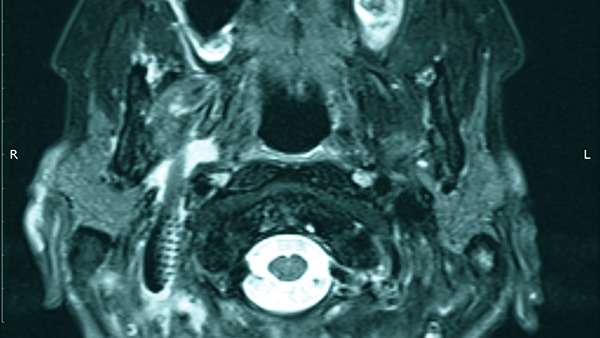

LifestyleՀամբուրգի 65-ամյա բնակչուհին դիմեց բժիշկներին՝ ասելով, որ չի կարողանում գտնել ատամները լվանալու ժամանակ կորցրած էլեկտրական խոզանակի կտորը: Բժիշկները նախ հետազոտեցին կնոջ ստամոքսն ու աղիները, բայց ոչինչ չհայտնաբերեցին և նրան ուղարկեցին տուն: Բայց մի քանի օր անց կինը կրկին դիմեց հիվանդանոց՝ գանգատվելով, որ ոչինչ չի կարողանում ուտել: Դիմածնոտային վիրաբույժը կնոջ բերանի խոռոչի փափուկ հյուսվածքներում 6 սմ երկարությամբ օտար առարկա նկատեց: Պարզվեց, որ դա հենց ատամի խոզանակի ջարդված կտորն էր: Վիրահատությունից հետո մի քանի օր անց կինը դուրս գրվեց: